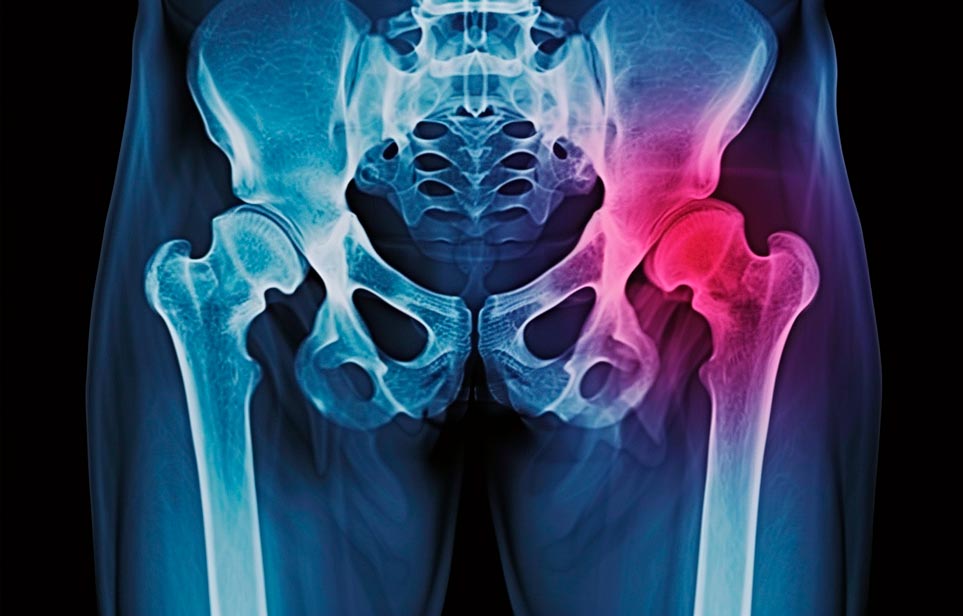

Реабилитация пожилых после перелома шейки бедра в Судаке

Такая травма в большей части случаев возникает у граждан преклонного возраста. При её появлении на протяжении длительного времени сохраняются болевые и неприятные ощущения в области паха, при которых серьёзно ухудшается качество жизни, возникает множество последствий для его жизни и здоровья.

По какой симптоматике можно определить перелом шейки бедра?

Выявить его можно по возникновению следующей тревожной симптоматики:

- Визуально повреждённая нога сокращается на несколько сантиметром из-за сокращения мышц.

- Стопа выворачивается наружу.

- В лежачем положении человек не может поднять ногу.

При такой симптоматике важно незамедлительно обращаться к специалистам для получения всей необходимой помощи, терапии и восстановления после перелома шейки бедра. Если не оказать помощи старику, то это приведёт к гноению, инвалидности, иным видам осложнений.